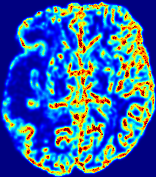

LesionRefer to captionRefer to captionRefer to captionRefer to captionRefer to captionRefer to caption𝐕rgbsubscript𝐕𝑟𝑔𝑏{\bf{V}}_{rgb}Refer to captionRefer to captionRefer to captionRefer to captionRefer to captionRefer to caption𝐕2subscriptnorm𝐕2{\|\bf{V}}\|_{2}Refer to captionRefer to captionRefer to captionRefer to captionRefer to captionRefer to captionRefer to caption3.53.53.52.82.82.82.12.12.11.41.41.40.70.70.70.00.00.0(mm/s)𝑚𝑚𝑠(mm/s)D𝐷DRefer to captionRefer to captionRefer to captionRefer to captionRefer to captionRefer to captionRefer to caption0.0200.0200.0200.0160.0160.0160.0120.0120.0120.0080.0080.0080.0040.0040.0040.0000.0000.000(mm2/s)𝑚superscript𝑚2𝑠(mm^{2}/s)Slice #1Slice #2Slice #3Slice #4Slice #5Slice #6

Figure 3: PIANO feature maps for one stroke patient, where the lesion is located in the left hemisphere. Top row: segmented stroke lesion region (white) on different slices, obtained from ISLES 2017. The corresponding slices for the PIANO feature maps are shown in the following rows.

For a better insight into an estimated velocity field 𝐕𝐕{\bf{V}} and diffusion field 𝐃𝐃{\bf{D}}, we compute the following maps: (1) 𝐕rgbsubscript𝐕𝑟𝑔𝑏{\bf{V}}_{rgb}: Color-coded orientation map of 𝐕=(Vx,Vy,Vz)T𝐕superscriptsuperscript𝑉𝑥superscript𝑉𝑦superscript𝑉𝑧𝑇{\bf{V}}=(V^{x},V^{y},V^{z})^{T}, obtained by normalizing 𝐕𝐕{\bf{V}} to unit length and mapping its 3 components to red, green, blue respectively; (2) 𝐕2subscriptnorm𝐕2\|{\bf{V}}\|_{2}: 222 norm of 𝐕𝐕{\bf{V}}; (3) D𝐷D: scalar field in Eq. 5.

Fig. 3 and Fig. 4 show the PIANO feature maps estimated from two ISLES 2017 patients: all are highly consistent with the lesion in both cases. Details of the blood flow trajectories are revealed in 𝐕rgbsubscript𝐕𝑟𝑔𝑏{\bf{V}}_{rgb} by the ridged patterns and the sharp changes of colors in the unaffected (right) hemisphere, while the flat patterns appearing within the lesion provide little directional information about the velocity and indicate low velocity magnitudes. Velocity magnitudes are more directly visualized via 𝐕2subscriptnorm𝐕2\|{\bf{V}}\|_{2}, from which one can easily locate the lesion where 𝐕2subscriptnorm𝐕2\|{\bf{V}}\|_{2} is low. D𝐷D also indicates lower diffusion values in the lesion, though with less contrast potentially due to the fact that it captures the accumulated effect of CA diffusion at the voxel-level.